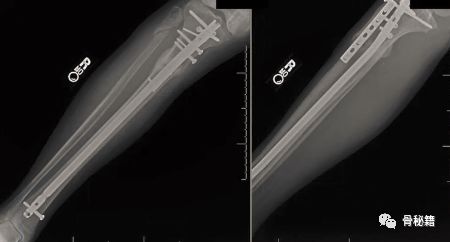

一个多阶段的胫骨骨折,看着移位不大

植入髓内钉后……

这样的骨折肯定长不上了,病人看了估计都会天天找你吧?翻修,近端加阻挡钉,小钢板